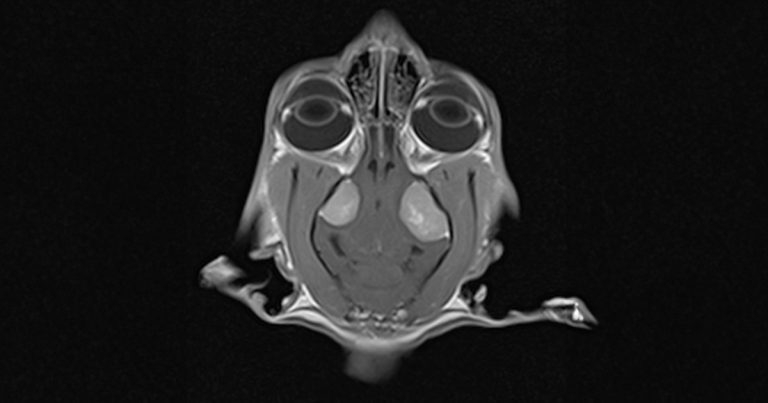

An MRI scan confirmed the presence of two symmetric lesions located in the region of the left and right temporal lobes.

Patient was admitted for MRI scans under general anaesthetic. An MRI scan of the brain confirmed presence of two symmetric lesions located in the region of the left and right temporal lobes. Both masses were oval shape. Left lesion was noticeable bigger 1.64cm high x 1.8cm long and 1.2cm wide compared to the right sided mass of 1.5cm high x 1.3cm long and 1cm wide.

MRI scan confirmed that lesions were causing severe mass effect resulting in marked transtentorial and cerebellar herniation and an evident dilation of the central canal, extending from the level of C2 to C6. The IV ventricle and part of the third ventricle had features of obstruction on the MRI scan.